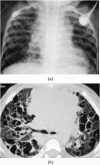

The objectives of this article were: (1) to review common and rare manifestations of systemic and pulmonary Langerhans cell histiocytosis, Rosai-Dorfman disease, Erdheim-Chester disease and juvenile xanthogranuloma; (2) to provide the reader with important pathologic, epidemiologic and clinical features of these diseases. The histiocytoses are a diverse group of diseases which typically manifest with multiorgan involvement. Understanding the pathologic, epidemiologic and clinical features of these entities can help the radiologist suggest an accurate diagnosis of histiocytosis when typical imaging features are encountered.